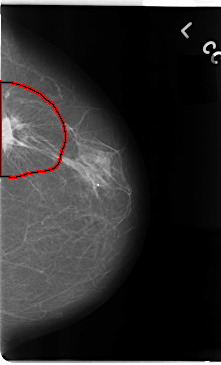

C_0079_1.LEFT_CC

FILE: C_0079_1.LEFT_CC.OVERLAY

TOTAL_ABNORMALITIES 1

ABNORMALITY 1

LESION_TYPE MASS SHAPE IRREGULAR MARGINS SPICULATED

ASSESSMENT 5

SUBTLETY 5

PATHOLOGY MALIGNANT

TOTAL_OUTLINES 1

BOUNDARY